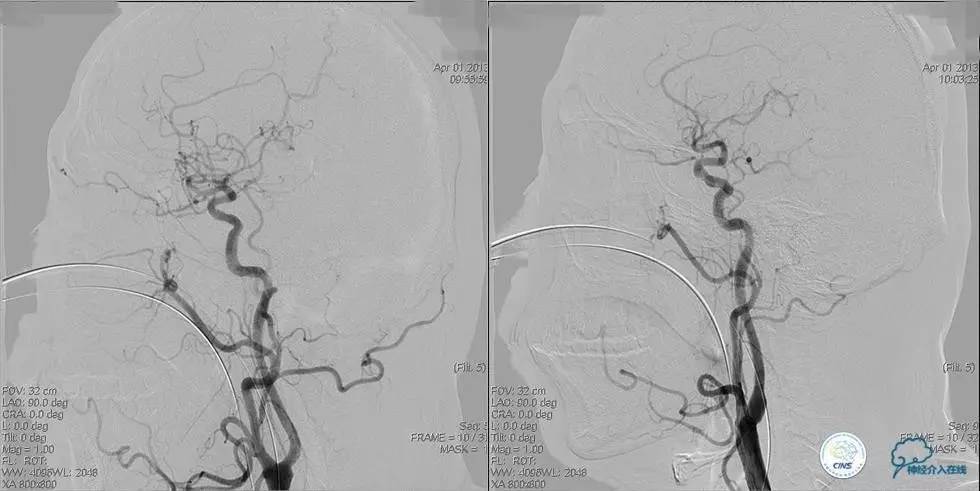

▼开通

出院情况:头晕症状消失,构音障碍缓解,进食无呛咳,饮水实验(-),右侧肢体远端肌力恢复到Ⅰ级。